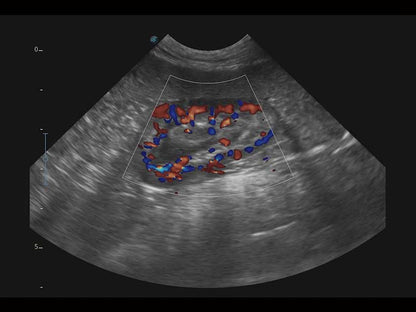

Az X Series Vet platform egy laptop kialakítású színes Doppler ultrahangrendszer, amely kiemelkedő képalkotó technológiáival van felszerelve, és professzionális állatorvosi szoftvereket kínál a kis kedvtelésből tartott állatoktól a nagy haszonállatokig. Kristálytiszta képalkotása és gördülékeny munkafolyamata új, továbbfejlesztett vizsgálati élményt biztosít, amely a magabiztos diagnózishoz szükséges pontosságot nyújtja.

Mivel az X Series Vet a SonoScape legújabb képalkotó technológiáit alkalmazza a nagy felbontású és mély penetrációjú képek előállításához, nagy mennyiségű diagnosztikai információ jeleníthető meg az ultrahang képernyőn. A továbbfejlesztett képminőség gyorsabb és pontosabb vizsgálatokat tesz lehetővé bármely állatfaj esetén.

A hatékonyságot, egyszerűséget és sokoldalúságot ötvözve az X Series Vet kiváló választás lógyógyászati vizsgálatokhoz. Speciális transzducerekkel és ló specifikus szoftverekkel felszerelve könnyedén készít lenyűgöző képeket az olyan alapvető alkalmazási területeken, mint az MSK, a reproduktív szervek vizsgálata, valamint a megfelelő penetrációt biztosítja hasi és kardiológiai vizsgálatokhoz is.